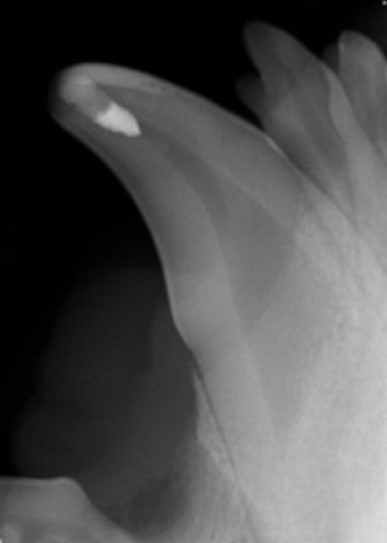

Figure 2: Canine tooth immediately after vital pulp therapy

Vital pulp therapy, also called vital pulpotomy, can be performed on fractured teeth with pulp exposure where exposure has occurred within 48 hours of treatment. In this procedure, a small amount of infected pulp is removed and a dressing powder called mineral trioxide aggregate (MTA) is placed on the pulp. The fracture site is sealed using composite--the same material used for filling cavities in humans. The dressing stimulates the tooth to form a bridge of dentin over the pulp and the tooth usually remains alive and healthy.